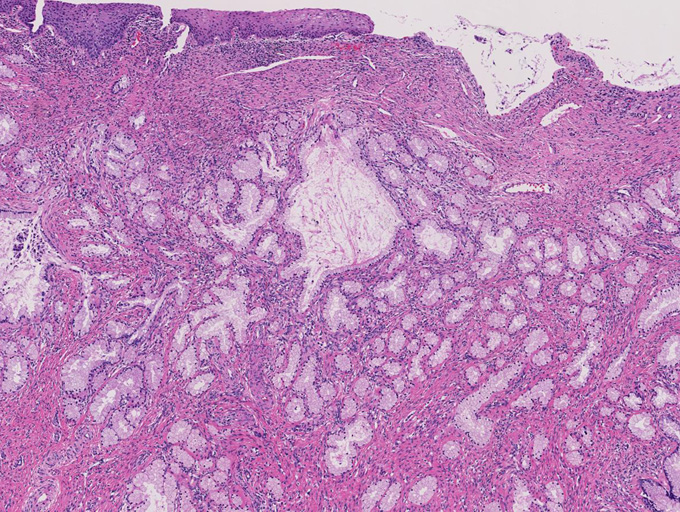

増生腺管上皮の細胞質は淡明ないし淡好酸性で, 核は小型で基底側に配列し、明らかな異型や重層化, 核分裂像を認めない。

腺管が破綻し, 間質への粘液逸脱と、それに対する間質反応も認めるが, この部分でも細胞異型は見られない。

しかしながら完全に異型がないとはいえず分葉構造を保持しているものの上皮の内腔への乳頭状増殖や重層化, 軽度から中等度の核腫大, クロマチン増加, 核分裂像をしめす腺が認められる---> with atypia

間質の一部には炎症細胞浸潤がめだつ。間質浸潤を疑う「折れ釘-->いびつなおれ釘のようなねじれた--」のような不整な形態の腺管は認められない。

LEGHは大型導管に類似した拡張腺管の周囲に中型から小型の腺管が分葉状に増生するのが特徴。小型腺管を構成する高円柱上皮細胞質は正常頸管腺上皮の細胞質が淡明あるいは, やや青白い色調を呈するのに対し淡明ないし淡好酸性となる傾向にある。

核は小型円形で基底側に配列し典型例では異型, 核分裂像は認めない。